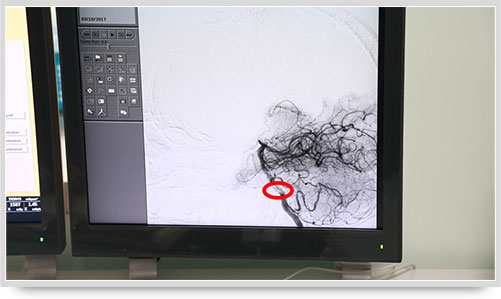

45岁的朱姓患者因“多发性腔性脑梗塞”头晕不明,接受了全脑血管造影术,术中显示他的颅内椎动脉血管痉挛(红圈内为病变部位)。据李主任介绍,以前像脑梗塞等脑血管疾病只能被定位到脑的功能区域,无法确定责任血管,而实施全脑血管造影术就能精准地找出病变血管,好比揪出了造成脑梗塞的“祸首”,大大提高了脑血管疾病的诊治水平。

之前,另一位61岁的李姓脑出血患者,康复治疗半个月后复查,也接受了全脑血管造影术,术中显示大脑前动脉A1段动脉瘤(不同维度显影,红圈内为动脉瘤瘤体)。像这样的病人,必须进一步进行手术治疗,及早清除动脉瘤,避免因瘤体破裂造成再次出血危及生命。